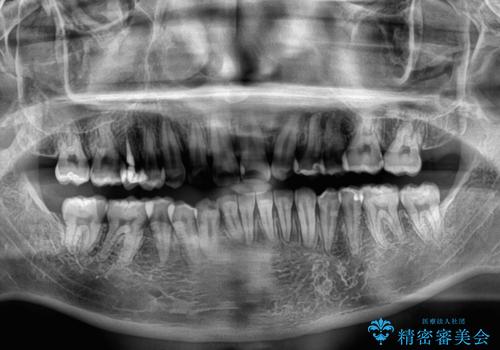

骨格的に、下顎が右側にずれており、左側の咬み合わせに鋏状咬合などのアンバランスが生じている状態でした。

また、上顎前歯に欠損が1本あり、上下ともに前歯部に叢生が認められ、下顎前歯の大半が隠れてしまうほどの過蓋咬合も認められました。

咬合平面を平坦にしながら前歯の咬み合わせを挙上し、デコボコと鋏状咬合も改善していくこととしました。

骨格的な左右差が大きかったため、上下の正中のズレや、左右奥歯の咬み合わせなどは妥協的な仕上がりとなりました。

骨格的なズレに対応するにはワイヤー矯正が至適であり、マウスピース矯正は選択しないようにお話をしました。